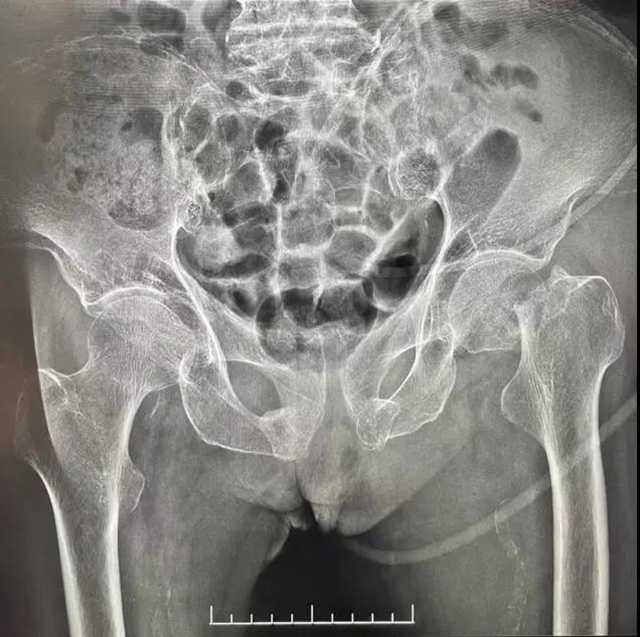

西南医大附院实施一例罕见儿童分裂手矫正手术“每个孩子都是上天赐予我们的礼物”遗憾的是上天也难免有不开眼的时候在生活中我们常会看到一些有着先天性缺陷的孩子刚出生就让父母一脸愁容不仅给今后的学习和生活带来诸多不便还会给幼小的心灵造成难以抚平的创...